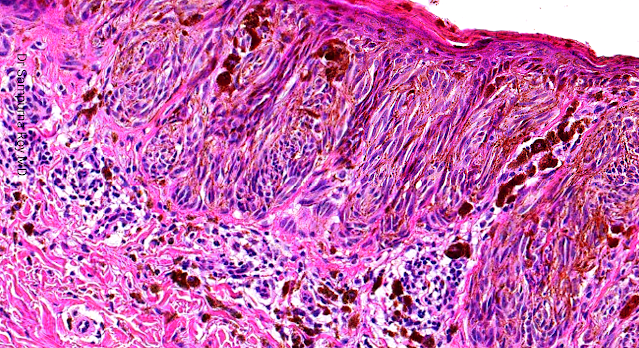

A 10-year-old boy, presented with an uniformly pigmented

lesion with regular margins. The lesion was located on the

medial aspect of the left knee.

Surgical excision with a 2-mm margin was performed.